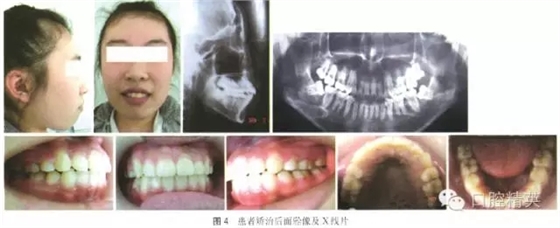

上下頜牙列排列整齊,上下前牙中線居中,雙側(cè)磨牙及尖牙關(guān)系中性,前牙覆牙合覆蓋正常,上下前牙牙軸改善。X線檢查顯示:未出現(xiàn)明顯牙根及牙槽骨吸收現(xiàn)象。治療后的面牙合像、曲面斷層及頭顱側(cè)位片(圖4)。治療前后頭影測量分析見表1。家長及患者對矯治效果非常滿意。治療結(jié)束后隨訪18個月未見明顯復(fù)發(fā)(圖5),全身狀況良好,精神面貌明顯改善。

640.webp (4).jpg